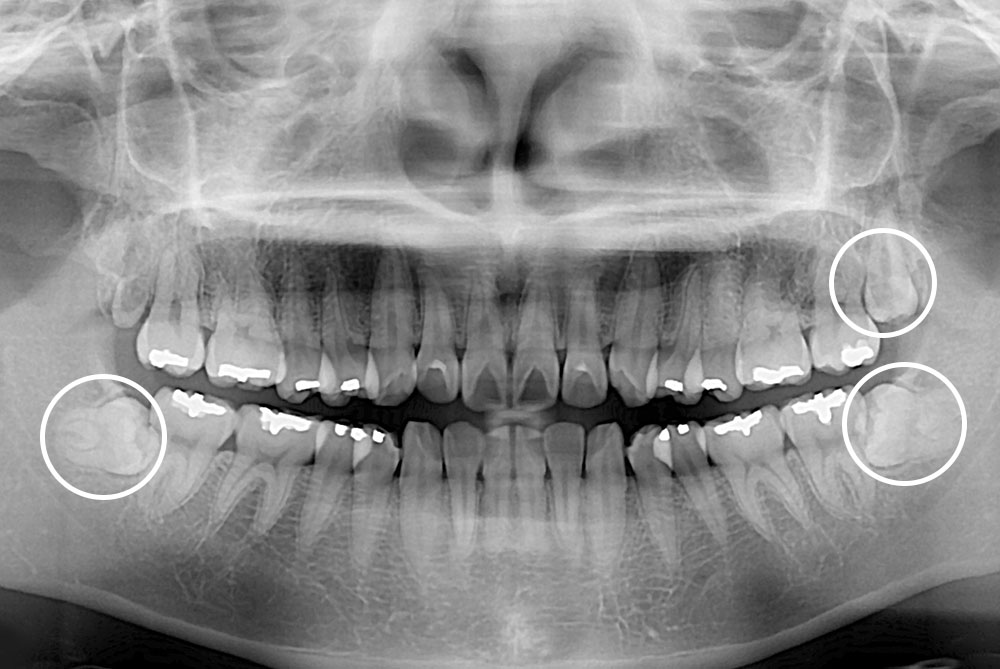

[사랑니] 매복 사랑니 발치

치료전 : 2017-06-07